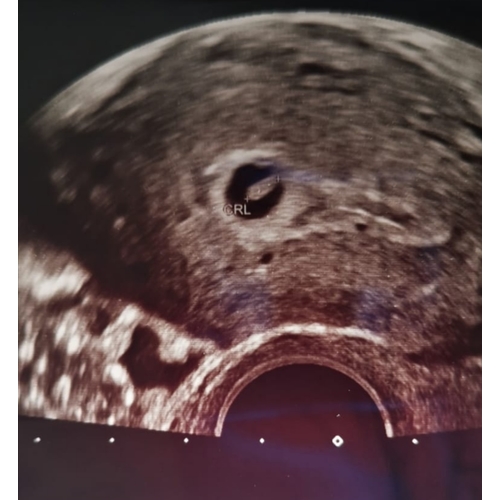

2 extra echo’s gehad voor de 12 weken echo. Waaronder een met 5+5 toen was ...

Dankje! Deze was met 5+5, nu ik ze zo even bij heb gepakt zie ik dat ik meer heb gehad dan ik dacht 🙈 ( dit ivm eerdere missed abortion ) ook nog met 6+4, 9+3 en toen de 12 weken echo. Zelf met 15 weken geslachts bepalende echo laten maken en toevallig vandaag de 20 weken echo gehad. 🎀💗